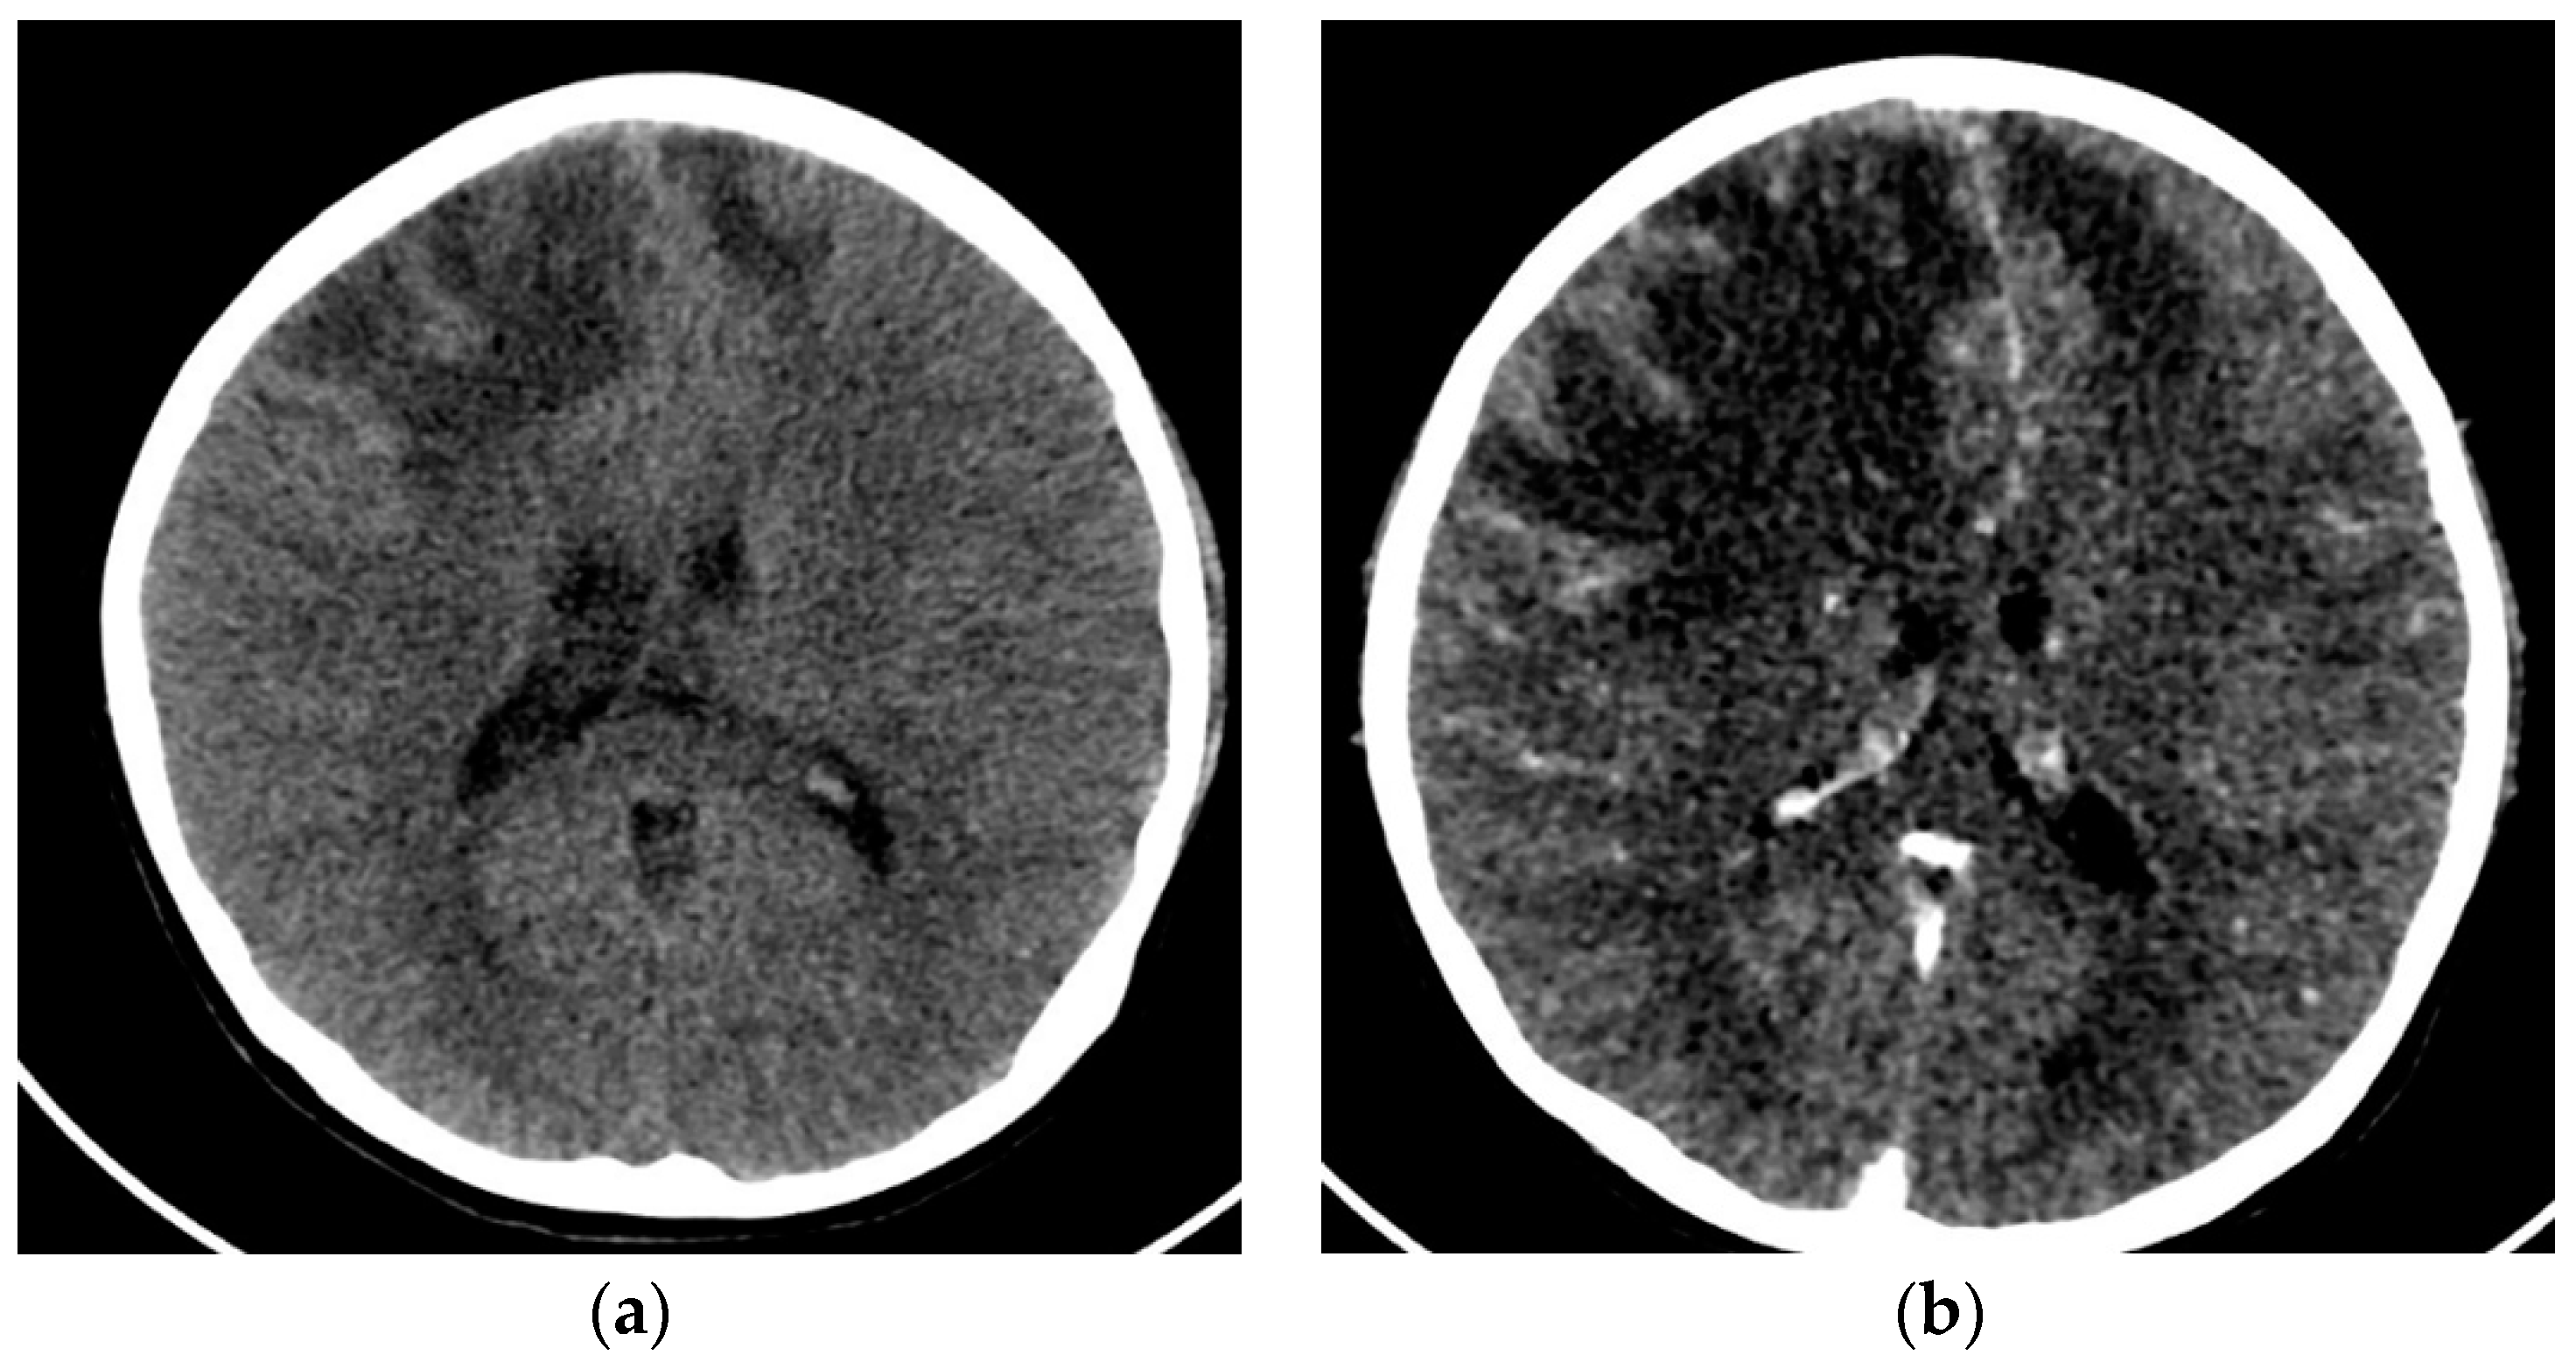

2.1. Case 1

2.2. Case 2

2.3. Case 3